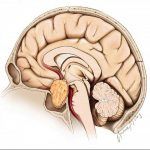

U Tuyến Yên | Bài giảng CĐHA *

U tuyến yên (Pituitary Tumors) là u lành tính, phát triển từ thùy trước của tuyến yên, đây là loại u thường gặp nhất trong các loại u vùng tuyến yên. U tuyến yên chiếm 10% khối u trong sọ, gặp độ tuổi 38-50, rất hiếm gặp ở trẻ em. Dựa vào sinh lý bệnh chia thành loại tăng tiết và không tăng tiết hormon…